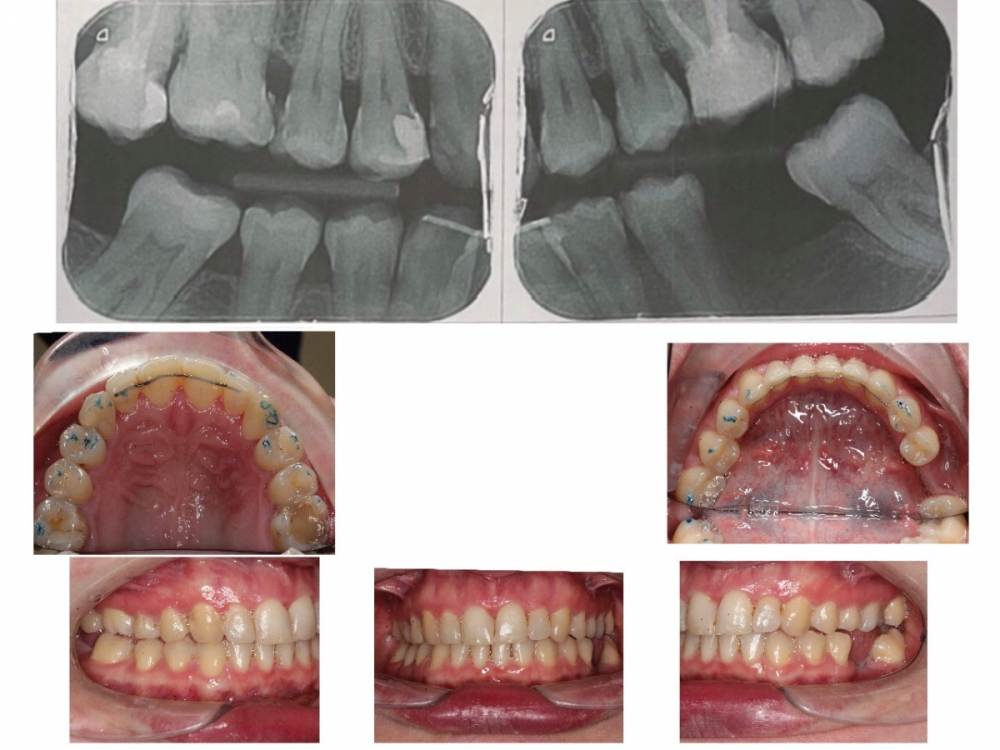

Здравствуйте, в стране проживания я прошла ортодонтическое лечение (3 года в брекетах). Меня не устраивает результат, но к сожалению все ортодонты тут с которыми я говорила не хотят ничего делать, тк их результат устраивает. У меня вопросы :

1. можно ли установить имплантанты внизу как 6 и 6 или 6 и 7

2. что делать с верхней семеркой ? Ее хотят удалить, не хотят ставить коронку.

3. что делать с окклюзией. Это действительно все нормально? Такой угол для 7го зуба это нормально? 2ая окклюзия с другой стороны это нормально?

4 стерся клык о брекет- как сделать улыбку снова симметричной ?

5 сколько продержатся зубы без лечения тут - на верхних зубах с 1й стороны кариес, нужны коронки на верхних 6 и 7 ( разные стороны)

какие способы решения проблемы существуют? Тк тут мне никто помочь не хочет, то я вижу выход только попробовать myobrace - вдруг он вернёт среднюю линию на место и сделает окклюзию лучше. как только станет проще путешествовать - ездить с маленьким ребёнком в россию, там мб поставить брекеты, коронки, имплантанты.

тут мне говорят что сделать апрайтинг невозможно , как и передвинуть среднюю линию, и все нормально с зубами. Что мне вообще делать и как жить?